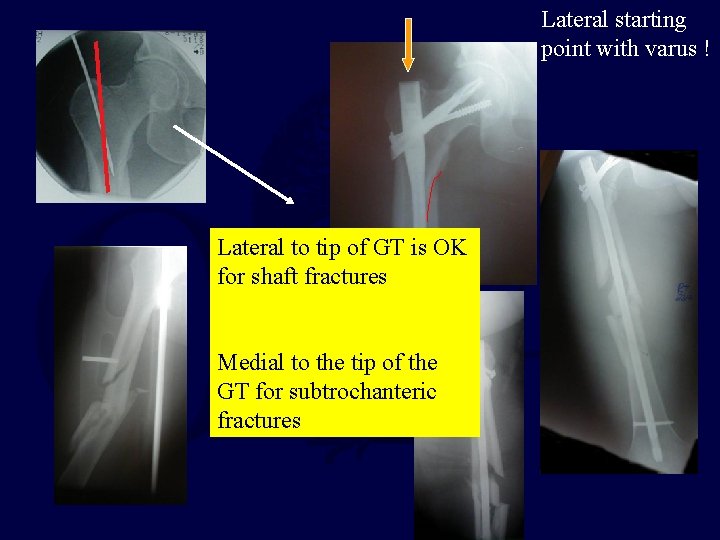

Lateral starting point with varus ! Lateral to tip of GT is OK for shaft fractures Medial to the tip of the GT for subtrochanteric fractures